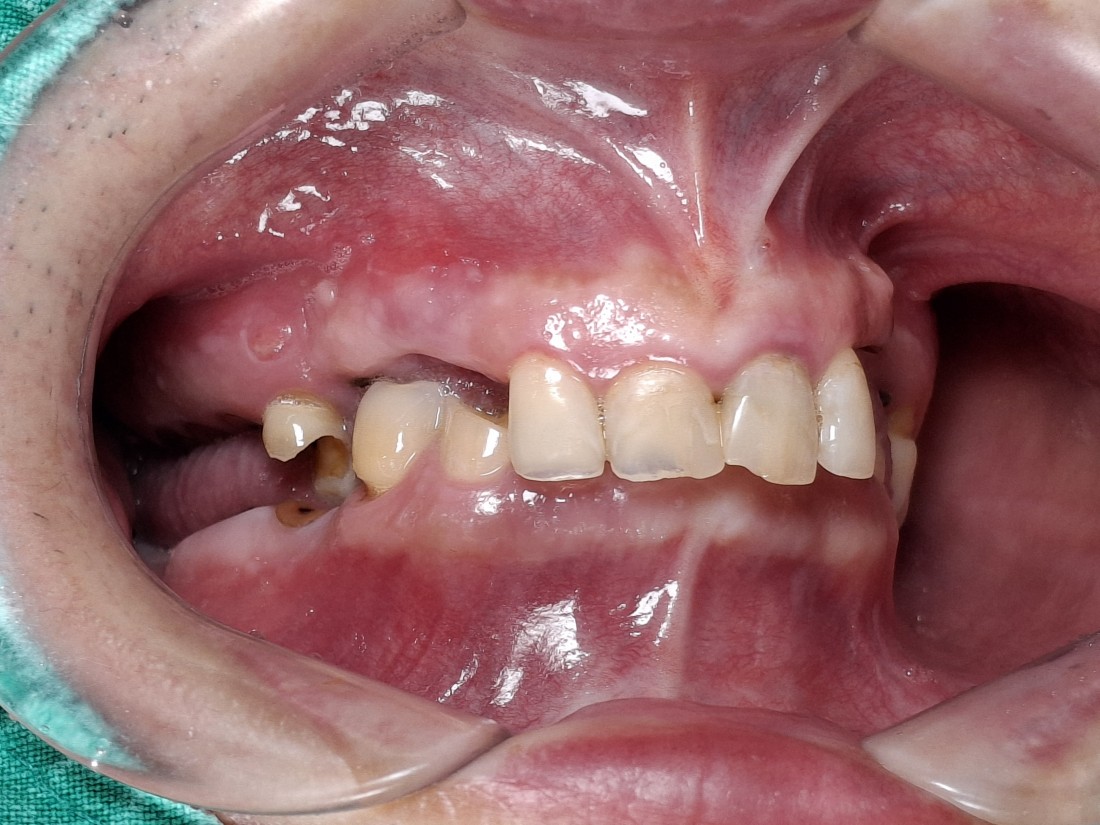

수완동 임플란트 치과는

수 백개의 임플란트 전/후 케이스 사진을

홈페이지에 공유하고 있습니다.

전체 임플란트부터

신경쓰이는 앞니 임플란트,

20대 / 30대 임플란트 케이스부터

80대가 넘는 분들의 케이스까지

정말 다양한 모든 케이스를 보유하고 있습니다.

다양한 각도의 임플란트 식립 전/후 사진으로

실력에 자신있는

수완동 임플란트 치과입니다.